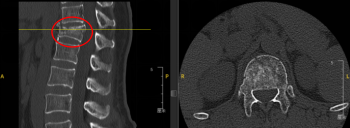

术前CT